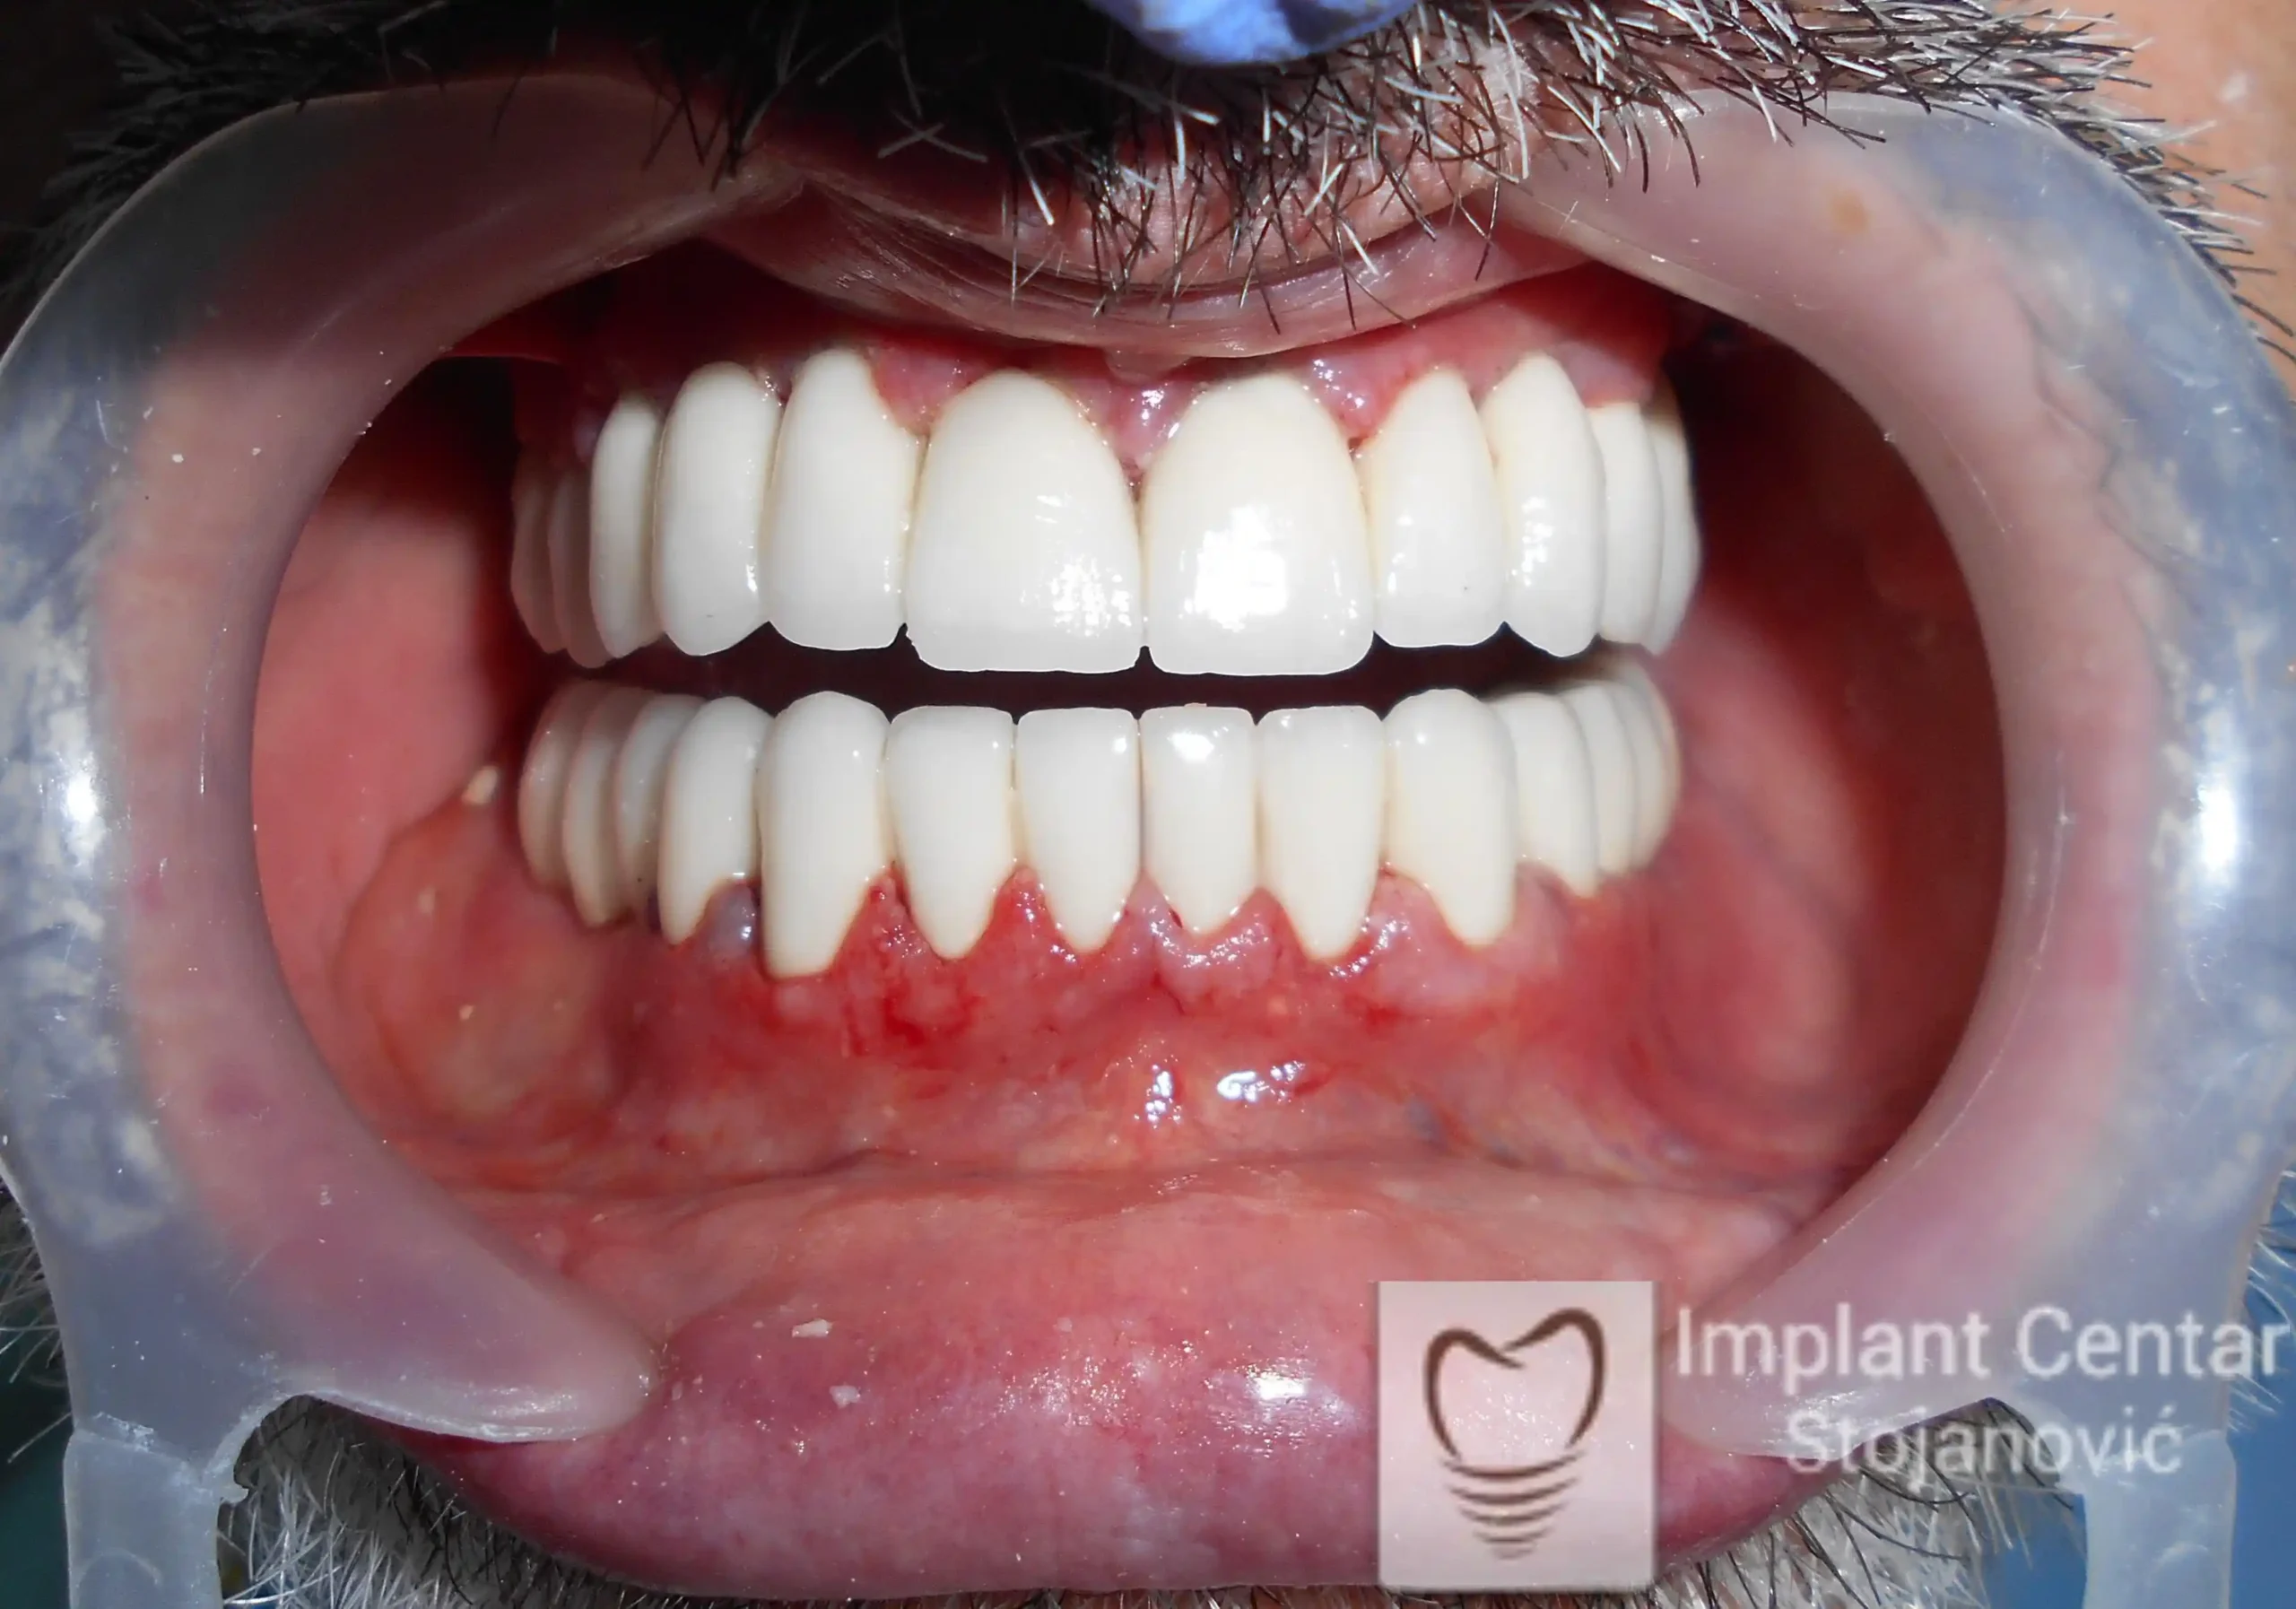

Pacijent sa rascepom usne, nepca i alveolarnog grebena uspešno je rehabilitovan fiksnim protetskim radom na implantatima. Pre dolaska u našu ordinaciju, pacijent je u gornjoj vilici nosio totalnu protezu preko preostalih zuba, dok je u donjoj vilici bio zbrinut parcijalnom mobilnom protezom. Tokom višegodišnje potrage za adekvatnim rešenjem, pacijent nije uspeo da pronađe zadovoljavajuću terapijsku opciju ni u zemlji ni u inostranstvu.

Tokom perioda oseointegracije, pacijent je bio zbrinut fiksnim privremenim krunicama, čime je već pet dana nakon intervencije obezbeđena potpuna funkcionalna i estetska rehabilitacija. Nakon završetka perioda integracije implantata, izrađeni su definitivni cirkonijum-keramički mostovi na implantatima.

Pacijent je izuzetno zadovoljan postignutim rezultatom, navodeći da po prvi put jasno oseća svoje nepce tokom žvakanja, kao i da se smeje sa punim samopouzdanjem.